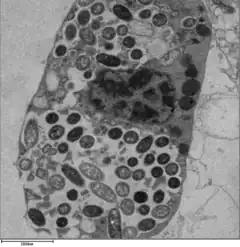

Legionella-containing vacuole

For Legionella to survive within macrophages and protozoa, it must create a specialized compartment known as the Legionella-containing vacuole (LCV).[37] Through the action of the Dot/Icm secretion system, the bacteria are able to prevent degradation by the normal endosomal trafficking pathway and instead replicate. Shortly after internalization, the bacteria specifically recruit endoplasmic reticulum-derived vesicles and mitochondria to the LCV while preventing the recruitment of endosomal markers such as Rab5a and Rab7a. Formation and maintenance of the vacuoles are crucial for pathogenesis; bacteria lacking the Dot/Icm secretion system are not pathogenic and cannot replicate within cells, while deletion of the Dot/Icm effector SdhA results in destabilization of the vacuolar membrane and no bacterial replication.[38][39]

L. pneumophila is able to invade and replicate within human alveolar macrophages. Internalization of the bacteria appears to occur through phagocytosis or coiling phagocytosis and is reliant on Dot/Icm type 4B secretion system (T4BSS). Once internalized, the Dot/Icm system begins secreting bacterial effector proteins that recruit host factors to the Legionella containing vacuole (LCV). This process prevents the LCV from fusing with the lysosomes that would otherwise degrade the bacteria. Vesicles of the host cell's rough endoplasmic reticulum are attracted to the LCV, and these vacuoles supply the LCV with necessary lipids and proteins.[13] LCV membrane integrity requires a steady supply of host lipids, such as cellular cholesterol and the cis-monounsaturated fatty acid, palmitoleic acid.[31][32] L. pneumophila replication occurs within the LCV. Once nutrients are depleted, the bacteria gain flagella and cytoxicity. To exit the host cell, L. pneumophila lyses the LCV and resides in the cytoplasm. In the cytoplasm, L. pneumophila inhibit organelle and plasma membrane function and structure which ultimately leads to osmotic lysis of the host cell.[33]